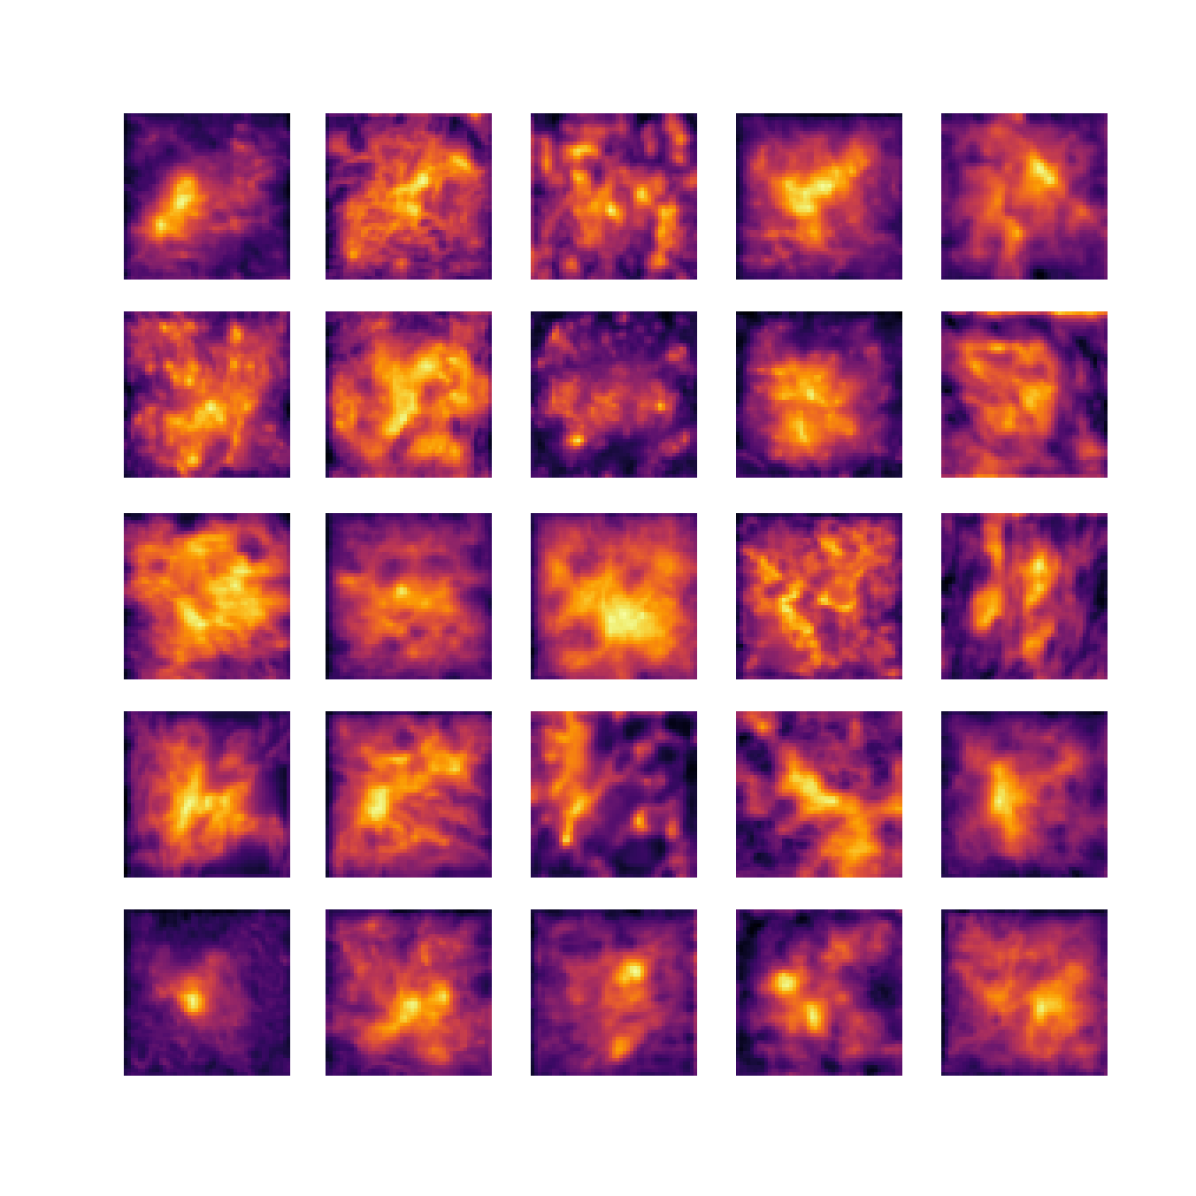

We also analyse the activation maps for each model using GradCAM as described in section S3. This offers more insight into the areas of the image which are contributing most heavily to the models’ representations. In Figure 4(b) we present some representative examples, however, a larger selection which was chosen at random is presented in Figures S10 to S25. The larger selection makes it easier to see the emergent patterns, including that privileged Siamese models tend to mainly identify features which are strongly present in both inputs, while unprivileged Siamese models tend to learn more diffuse features that are not specific to one cell phenotype or image region. TriDeNT ♆ incorporates both sets of features, learning both features specific to the privileged data and more the general features associated with unprivileged Siamese networks.

We can see in Figure 4(b) panel A that for ERG, the privileged Siamese model focuses almost exclusively on any nuclei which could be endothelial cells. As there are very few endothelial cells in the dataset, it could be an effective strategy to identify anything that could potentially be an endothelial cell to minimise the difference between the representations of the H&E model and the IF mask model. In the corresponding unprivileged Siamese image, we see that the model identifies some of these nuclei, albeit less strongly, but also focuses heavily on the other tissue and even the background, while strongly fixating on two spots of debris in the center of the image. This model has less ‘incentive’ to learn the weak features related to endothelial cells as these occur rarely and are not easy to detect, while more generic strong features such as the presence of connective tissue and the prevalence of background are more common and predictable from augmented images. We see that TriDeNT ♆ combines these two feature sets, strongly identifying nuclei while also identifying the connective tissue.

In panel C we see a similar pattern, with the privileged Siamese model fixating solely on the nuclei, while the TriDeNT ♆ model takes a more balanced approach. The unprivileged Siamese model appears to focus on a single cluster of nuclei while neglecting others, and similarly identifies an area of fibroblasts with its distinctive pattern but does not others.

In contrast to panels A and C which represent models with poor privileged Siamese results, panels B and D represent models whose privileged Siamese results were comparable to both TriDeNT ♆ and even the supervised baseline. It is therefore interesting to note that there are far more similarities between the privileged Siamese and TriDeNT ♆ models in both cases. Particularly in panel B, TriDeNT ♆ and the privileged Siamese model return virtually identical heatmaps, with both strongly identifying epithelial nuclei and neglecting the same areas of connective tissue. The unprivileged model in this case appears to focus solely on the centre of the image, giving a significantly different heatmap to the other panels.

Panel D again shows the previous pattern, with the privileged Siamese model identifying the features strongly present in the privileged data – fibroblasts – while neglecting the nuclei present. TriDeNT ♆ also strongly identifies the connective tissue, but, unlike the privileged Siamese model, does not completely neglect the nuclei. The unprivileged Siamese model primarily identifies background, and does not appear to identify the nuclei in this example.